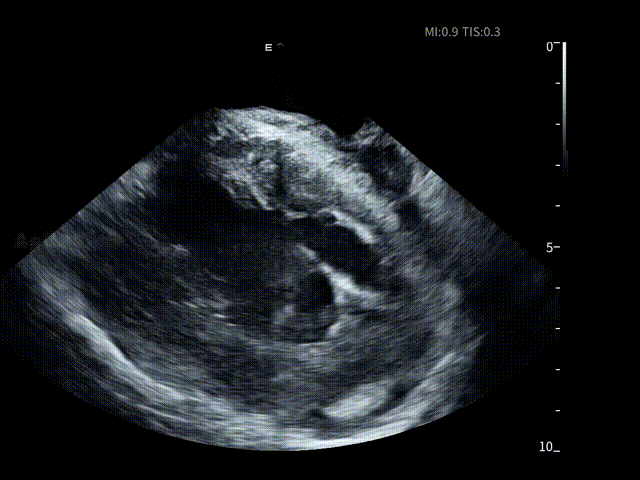

同样,在消融手术开始前,薛枫教授将ICE导管经股静脉穿刺进入右房进行术前筛查,术者对左心房、左心耳及心包区域进行了系统性扫查,在一站式手术开始前评估该患者不存在左房血栓情况,并进行术前心包监测。

AgileView™ ICE 的高清实时超声成像使潜在风险在早期即可被发现与排除,让后续操作始终建立在“可视、可控”的安全基础之上,有效提升整体手术安全性。

术前心包-有明显积液

在全球最细7.5Fr ICE的持续影像引导下,手术路径清晰。随后薛枫教授在ICE下进行了房间隔穿刺,见明显tenting现象。

随后,助手在AgileView™ ICE主机上,切换到了“PFA预设模式”下进行导管消融,在实时高清影像的指导下,PulseSelect™脉冲消融导管经导丝引导安全进入左心房,先后完成双侧肺静脉隔离,ICE PFA预设模式下可见画面成像清晰,导管贴靠良好,整个消融过程顺利高效,消融时间仅21分钟。术后患者恢复良好。

房间隔穿刺

ICE指导下房颤消融